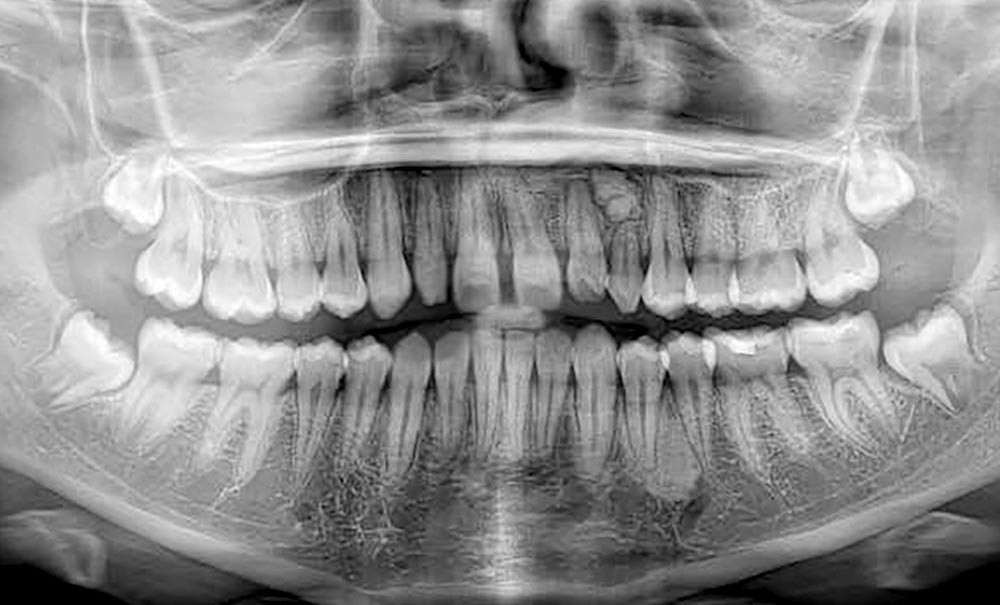

Les objectifs de traitement ont été atteints.

L’esthétique du sourire a été améliorée avec l’augmentation de la visibilité des dents maxillaires, ainsi que la restauration des incisives latérales au composite.

Le profil est plus harmonieux grâce à une diminution de la prochéilie mandibulaire par redressement de l’incisive mandibulaire (fig. 16- 18).

L’auto-transplantation de la 23 sur l’arcade, qui était en position très défavorable, et malgré un apex fermé présente de bons résultats. La radiographie rétro-alvéolaire (fig. 19) montre une intégrité de l’état radiculaire de la dent auto-transplantée. Un suivi régulier reste cependant nécessaire.

Le traitement a duré 1 an et 9 mois. L’auto-transplantation dentaire reste une technique de choix dans les cas où les dents se trouvent en position défavorable. Cependant, il s’agit d’une technique très chirurgien-dépendant qui nécessite un suivi régulier.